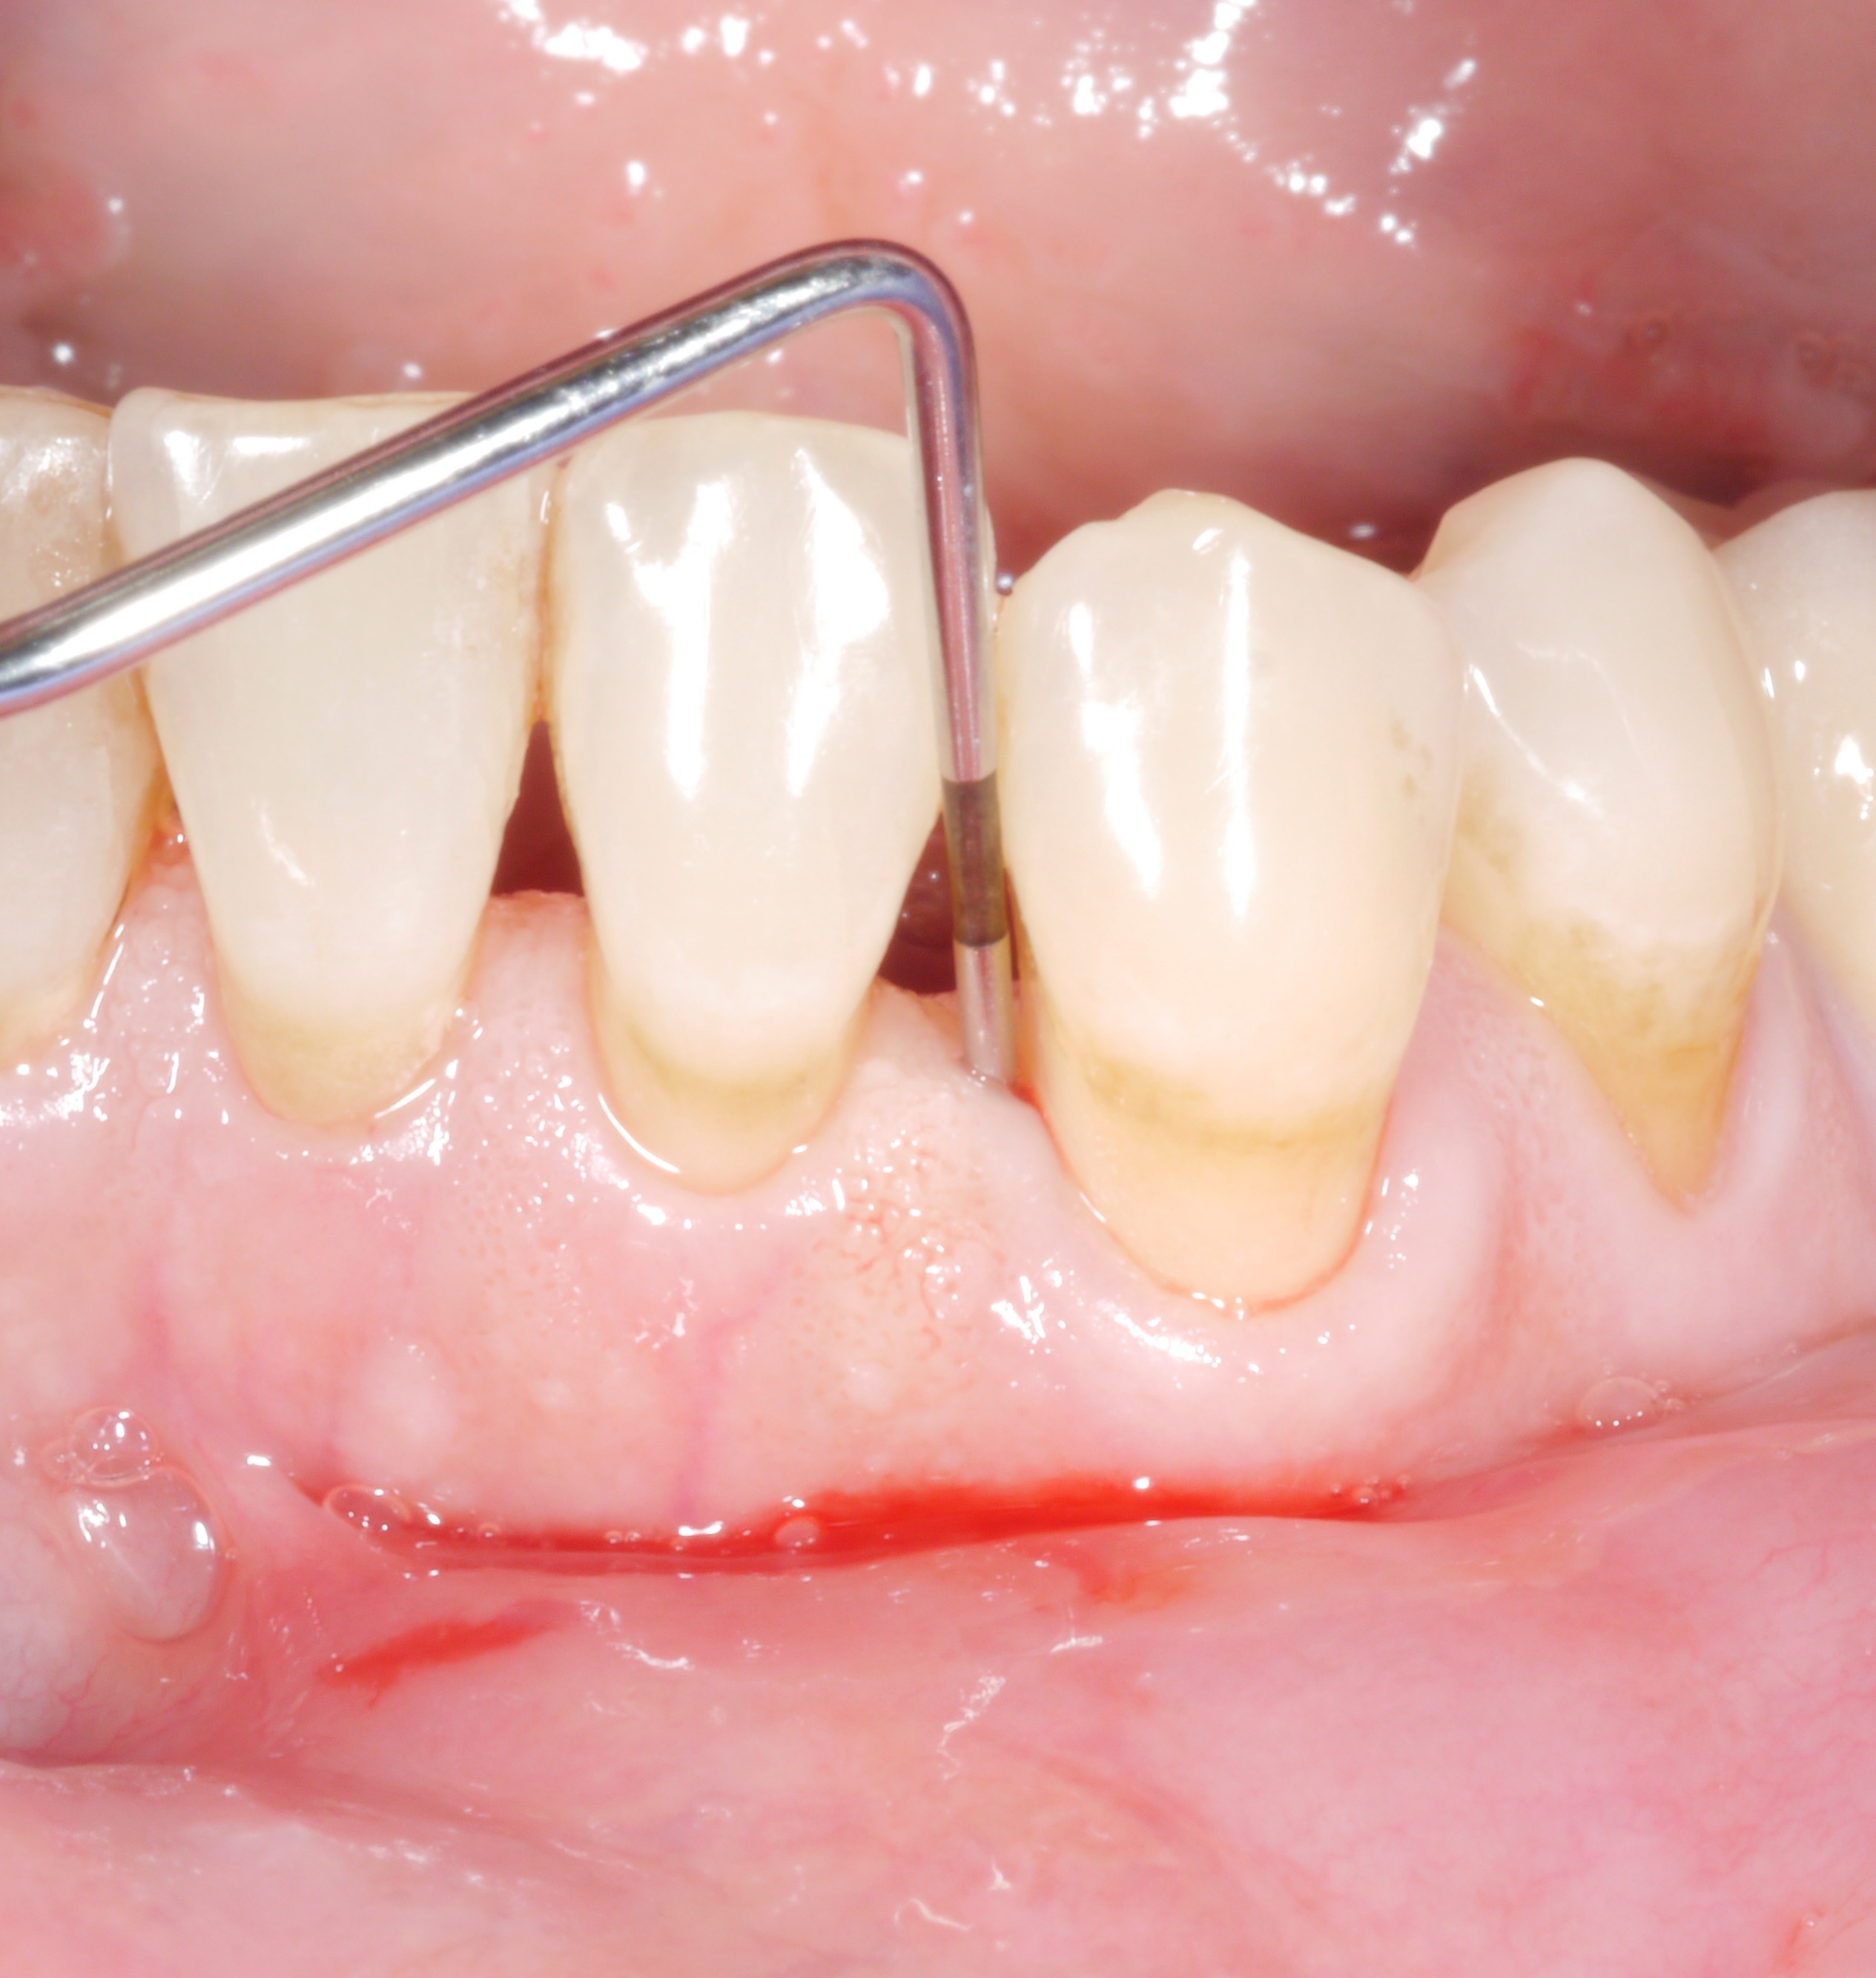

C'est une situation que nous connaissons bien : après la phase active du traitement, presque toutes les dents du patient ne sont plus affectées par l'augmentation de la profondeur de sondage des poches. Cependant, il reste encore un ou deux endroits où l'objectif du traitement n'a malheureusement pas été atteint. On peut alors se poser la question suivante : “ Quelle est la gravité de la situation ? Une seule poche de 6 ou 7 mm, cela ne peut pas faire une grande différence ?

Toutefois, les dentistes ne devraient pas se contenter de profondeurs de sondage résiduelles. En effet, même des profondeurs de sondage résiduelles de plus de 4 mm constituent un problème, du moins à long terme, tant pour la dent concernée que pour le reste de la dentition.

Les données d'une étude suisse, qui a suivi environ 170 patients en traitement d'entretien sur une période moyenne de 11 ans, ont montré très clairement le problème posé par les profondeurs de sondage résiduelles individuelles :

• Des profondeurs de sondage des poches résiduelles individuelles de 6 mm ou plus constituaient un facteur de risque de dégradation de la santé parodontale générale et de perte de dents.

• La profondeur de sondage de plusieurs poches résiduelles de 5 mm ou plus était également un facteur de risque de détérioration de la santé parodontale générale.

• Les saignements au sondage doublent le risque de perte ultérieure de dents.

• Le risque de perte de dents était presque 8 fois plus élevé pour une profondeur de sondage de 5 mm, environ 10 fois plus élevé pour une profondeur de sondage de 6 mm et plus de 60 fois plus élevé pour une profondeur de sondage de 7 mm !

Conclusion : l'objectif du traitement devrait être d'obtenir des profondeurs de sondage des poches de 4 mm maximum et une absence d'inflammation !